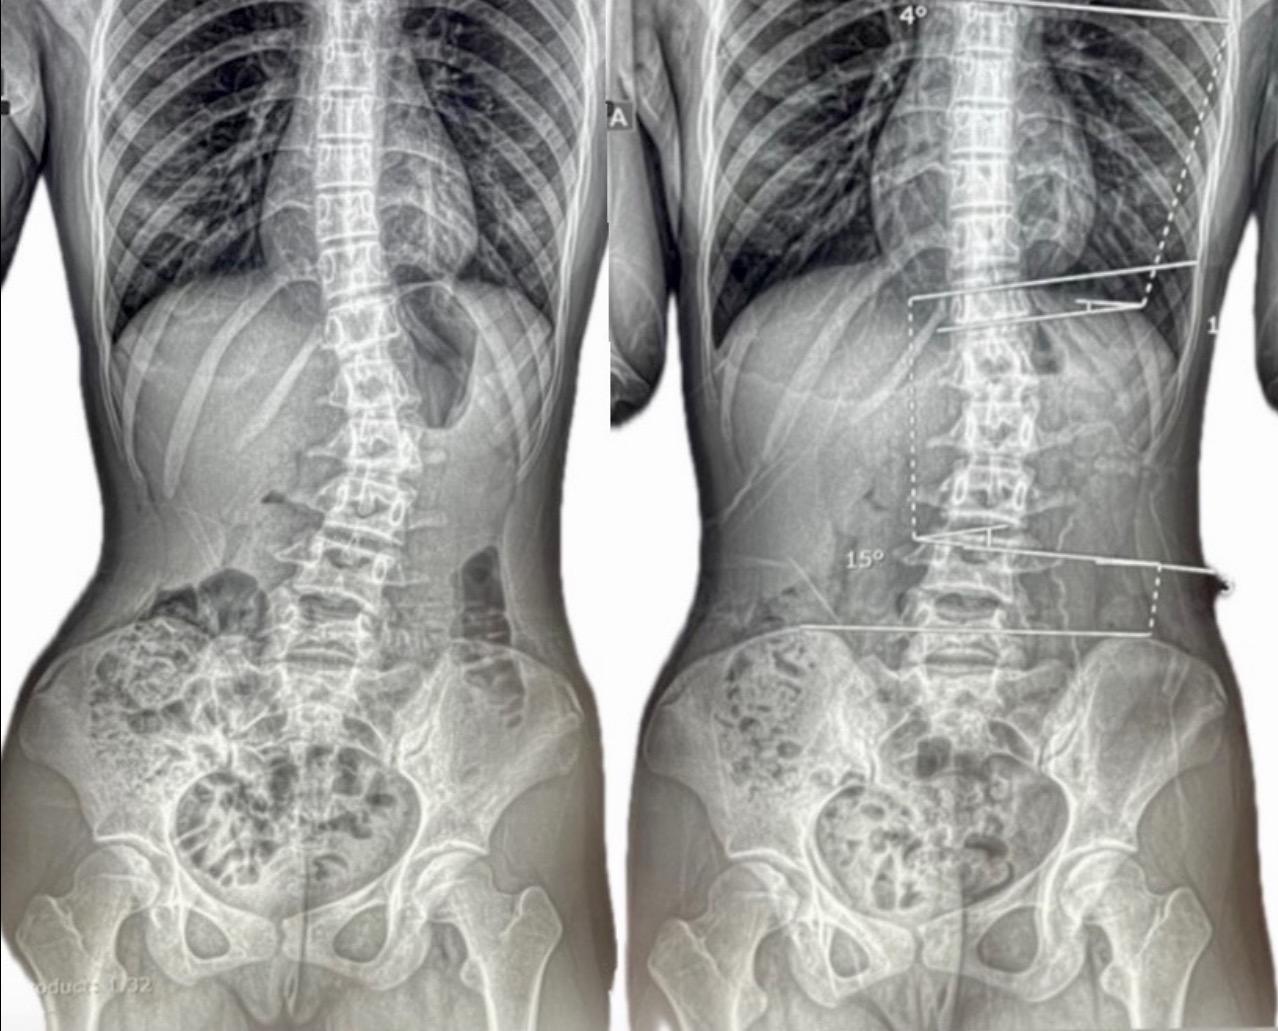

高校生の改善例(女の子)

当院のホームページをご覧になられ親御様よりご連絡いただきました。側彎症に伴う脚長差や腰背部の筋の張りの左右差などが顕著ではありましたが、側彎の角度における改善からそれらの状態にも改善がみられるようになり安定もしてきました。これからさらなる改善の可能性へと向け二人三脚で取り組んでいければとの思いがありましたが、まだ施術の途中ではありましたが、一身上のご都合によりここまでの施術となりました。

※これは個人の感想と画像の結果であり施術の効果を保障するものではありません。また効果には個人差があります。